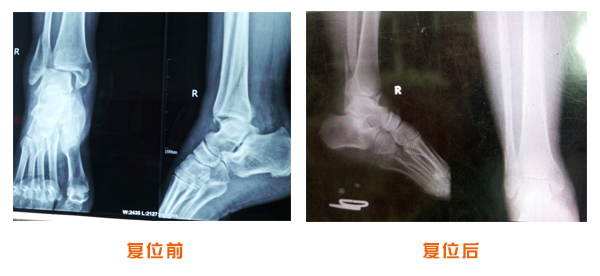

肘關節脫位骨折治療前后對比

踝關節脫位骨折治療前后對比

尺橈骨骨折治療前后

尺橈骨克雷氏骨折治療前后